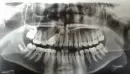

Дочери 11 лет 5 месяцев. Случайно на приеме стоматолог обратила внимание на аномальную четверку сверху справа.

После панорамного снимка обнаружилось, что она закрыла проход клыку, который остался в десне, сделали К/Т (клык достаточно далеко). Врач ортодонт предлагает удалить клык и (возможно) четверку. Но тогда ребенок в 11 лет останется уже без двух коренных зубов.